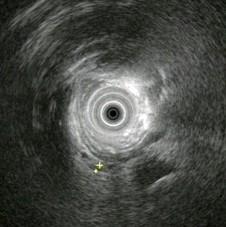

问题 男,42岁,右上腹绞痛反复发作二年,此次发病三天,发冷,发热(38.9℃),,查:巩膜明显黄染,超声内镜如图中病变可能的诊断是 ( )

选项 A、胰腺囊腺癌 B、胆总管结石伴扩张 C、胰腺囊肿 D、慢性胰腺炎伴胰管结石 E、正常

答案 B